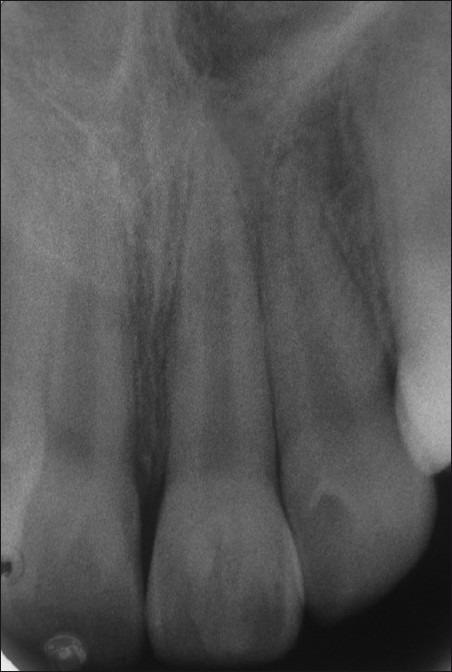

Talon cusp is a relatively uncommon developmental anomaly characterized by cusp-like projections, usually presenting on palatal/lingual surface of the anterior teeth. This cusp resembles an eagle's talon, and hence the name. Normal enamel and dentin covers the cusp, which may or may not contain an extension of pulp. Presence of this anomalous cusp on the facial surface of an anterior tooth is a rare finding and very few cases have been reported in the literature. In most instances, such cusps are associated with clinical problems such as poor esthetics and caries susceptibility. Management of such cases requires a comprehensive knowledge of the clinical entity as well as the problems associated with it. This case report presents a facial talon cusp on the maxillary left central incisor of a 10 year old boy, which was conservatively treated. Vitality of the affected tooth was maintained and followed up for a period of 1 year.